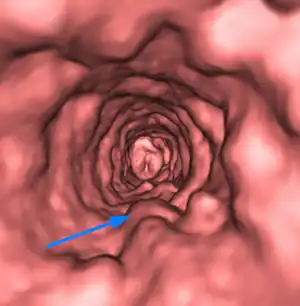

| Volumetric CT rendering of multiple tracheal papilloma (arrow). | |